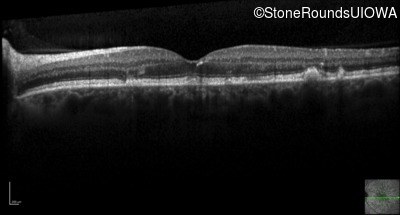

Optical Coherence Tomography - Right - 20/20 -1 sc

Exemplar / OCT Stack